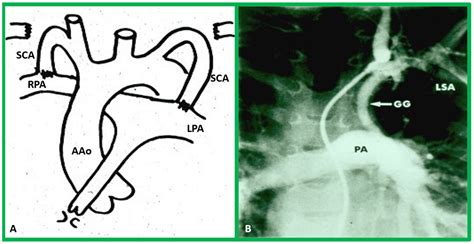

The severity of the condition often depends on the arrangement of the great arteries—the aorta and the pulmonary artery. In many cases, these arteries are transposed, which can lead to life-threatening complications if not addressed early. The primary clinical concerns include:

1. The Norwood Procedure (or shunt placement): Often performed in the first weeks of life to ensure adequate blood flow to the lungs or the body.

2. The Glenn Procedure (Bidirectional Glenn): Usually performed between 4 and 6 months of age, this connects the superior vena cava directly to the pulmonary arteries.

3. The Fontan Procedure: Typically performed between ages 2 and 5, this creates a final pathway for blood returning from the lower body to flow directly into the pulmonary arteries.